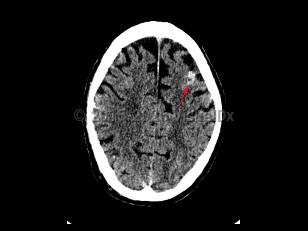

NeurocysticercosisNeurocysticercosis

Subarachnoid hemorrhageSubarachnoid hemorrhage